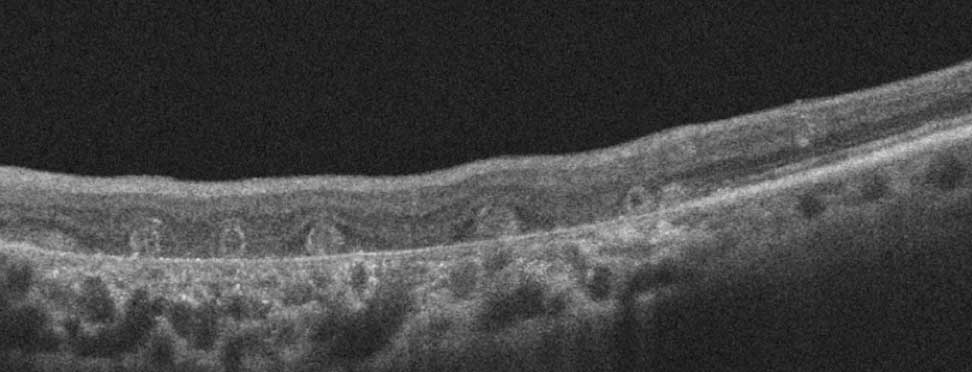

Here there is loss of the regular macular depression. There is a bright line present on the surface of the retina. In addition, there is separation of the retinal layers in the inner retina.

The patient was diagnosed with a schisis secondary to an epiretinal membrane. This complication is seen in over 50% of ERMs (video).